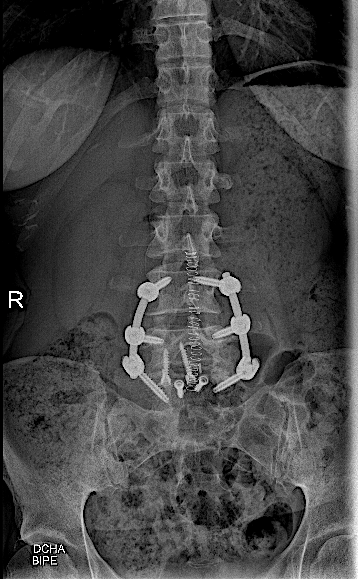

Tras la fijación percutánea, la paciente seguía presentando lumbalgia mecánica (de menor intensidad). Tras agotar opciones de tratamiento conservador, atribuimos como causa la discopatía incipiente L4-L5 (que había progresado).

Se intervino mediante un abordaje abierto (me parece muy a tener en cuenta que, las reintervenciones de los niveles adyacentes en cirugías percutáneas (MIS) deben realizarse en abierto para conectar el sistema!!) sin complicaciones, con buen resultado radiológico y clínico inicial. La paciente fue remitida a Rehabilitación.